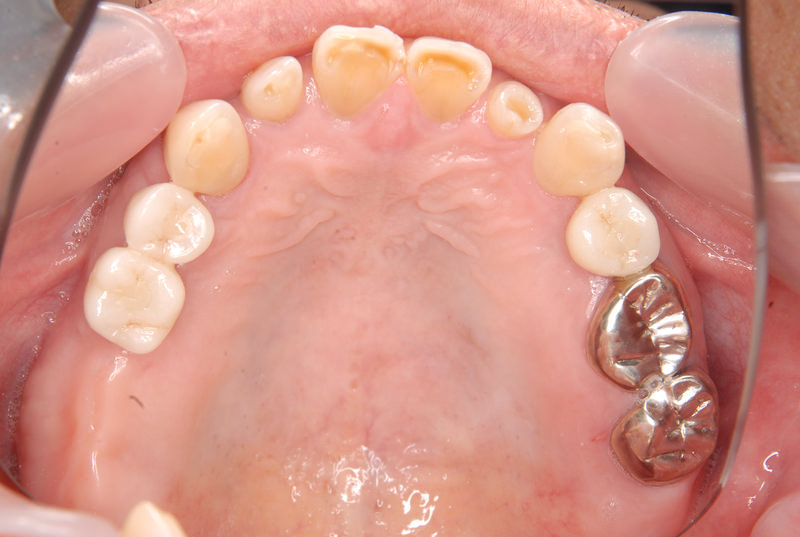

症例140代 男性 主訴 奥歯に歯を入れたい、しっかり噛みたい

治療前

治療後(5年経過)

主訴 奥歯がない為、食事が不自由である。入れ歯は煩わしいので、固定制のインプラントにして欲しいと訴え来院。口腔内全体で6本のインプラントを埋入。仮歯にて神経筋機構、顎関節のバランスを整え、リハビリを経て、約5ヶ月後にジルコニアを装着。

リスクとしては、外科的侵襲がある。デメリットは、保険外診療の為、経済的負担がある。

費用 316万(税込) (オペ・仮歯・最終補綴物まで含む)